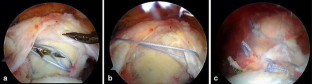

Fig. 1